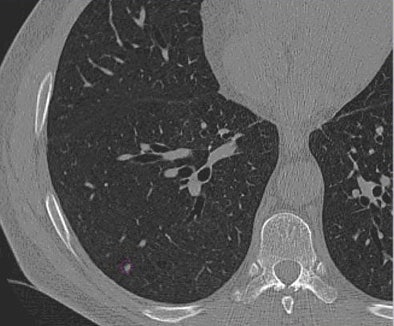

![]() |

| Images of solid lung nodules include uncompressed CT data (above), 24:1 compression (below), 48:1 compression (next down), and 96:1 compression (bottom). CAD detection performance of solid lung nodules greater than 4 mm in size did not suffer until 48:1 compression, and was found to be robust up to 96:1 even when the subjective visual appearance of the compressed images was degraded. The results suggest that 3D lossy wavelet compression can be performed without significant loss of CAD detection performance, which can minimize data storage and ultimately facilitate the implementation of CAD technology in a PACS environment. Images courtesy of Philippe Raffy, Ph.D. |